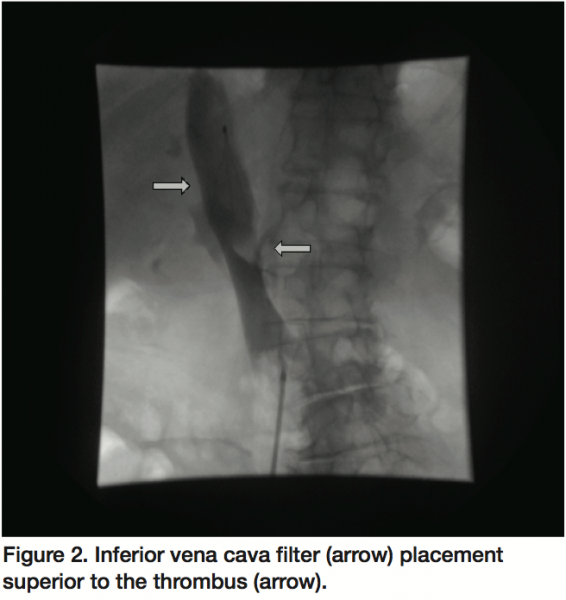

Preceding IVC filter placement, a venogram showed a large filling defect, consistent with a large thrombus, primarily adherent to the medial aspect of the IVC at the origin of the left renal vein (Figure 1). The superior portion of the thrombus had a mobile appearance which was concerning for impending rupture and embolization. A retrievable IVC filter (Celect, Cook Medical, Bloomington, Indiana) was successfully placed between the thrombus and the IVC-right atrial junction (Figure 2). Subsequent to IVC filter deployment, rheolytic thrombectomy (AngioJet, Medrad, Inc., Minneapolis, Minnesota) was performed with 5 consecutive passes within the IVC with significant reduction of thrombotic burden (Figure 3). Final venogram showed a very small residual adherent thrombus without evidence of a mobile component (Figure 4). The patient eventually underwent colonoscopy, which divulged stage 1 colon cancer involving the cecum and consequently, underwent successful partial colectomy with an uncomplicated recovery.